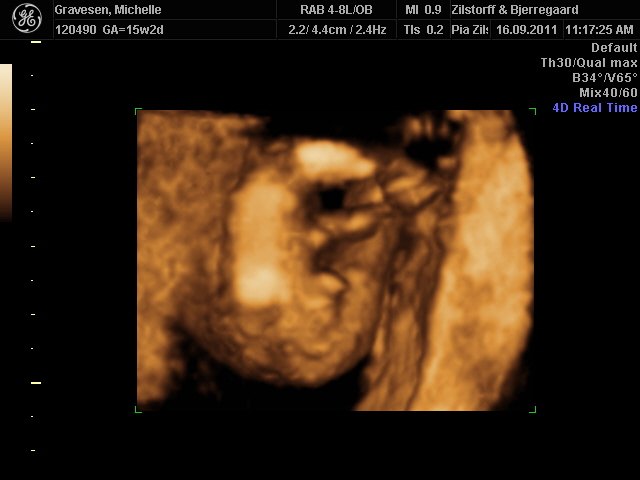

prøver lige at sætte to billeder ind. den ene fra 1. kønsscanning den anden fra 2. kønsscanning.

Hvad synes i? Udvikler barnets sig i ret af dreng eller pige?